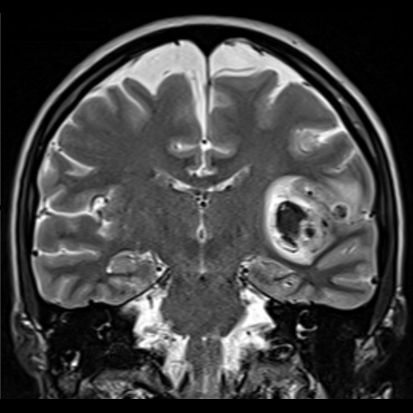

40 yaş, K

Ateş, bir haftadır artan baş ağrısı, yeni gelişen bilinç bulanıklığı

MCA bifurkasyon anevrizma ve parankim hematom

Sol MCA Segmet M2-3’te Sakküler Mikotik Anevrizma Rüptürü

Enfekte intrakraniyal anevrizma rüptürü